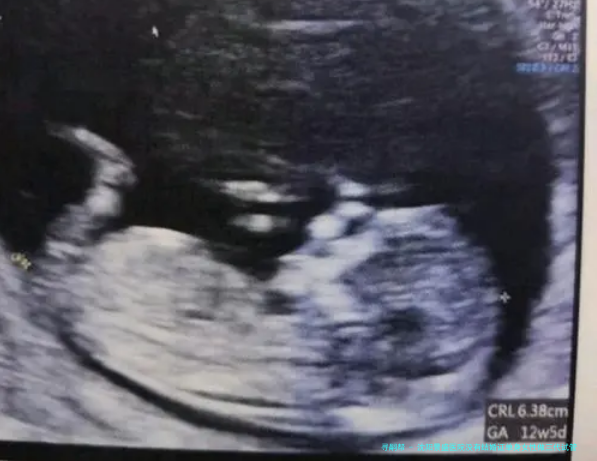

沈阳景盛医院的三代试管婴儿流程严格执行国家标准,并由资深医师团队悉心操作。整个流程可概括为以下若干个阶段:促排卵期、助孕及精子采集、胚胎培养、基因检测、胚胎移植等方法。每个阶段都需通过谨严的评估和监控,保障安全高成效完毕。

试管移植流程通常需要在促排卵期了结后进行。起首,医生会将检查筛选后的优良胚胎移植女性宫腔内。移植手术时间约为五至十分钟,麻醉形式为部分麻痹。术后患者须要躺床歇息两小时左右,观察身体状况。之后,患者须要定期监测受孕情况,并根据医生的指导进行后续的安胎护理。